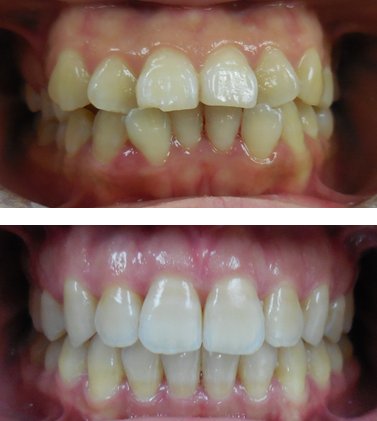

The mission of Shu Ping Rong, DDS, is rooted in a patient-centered philosophy that blends scientific precision with humanistic care. Dr. Rong believes that dentistry is not merely about treating teeth but about fostering lifelong oral health, boosting confidence, and improving quality of life. This ethos is evident in her practice's emphasis on preventive care, advanced treatments, and personalized attention. Services encompass a full spectrum of general dentistry, including routine cleanings, dental consultations, emergency care, root canals, bridges, and endodontics. Her expertise extends into specialized areas such as periodontics, laser dentistry, cosmetic dentistry, and orthodontics & dentofacial orthopedics, making her a one-stop solution for complex dental needs. Patients frequently seek her out for dental emergencies, bridges, and cleanings, reflecting her reliability in both urgent and routine scenarios.[1][2]

What truly sets Dr. Shu Ping Rong apart is her unique value proposition: a rare fusion of multilingual accessibility, elite certifications, and a track record of prestigious accolades. Fluent in English, Mandarin, and Cantonese, she bridges cultural gaps in New York's diverse Chinatown community, ensuring clear communication and culturally sensitive care. As an Invisalign VIP Platinum Plus Provider for both adults and teens in 2018, she excels in discreet orthodontic solutions, complemented by her extensive orthodontic training. Her practice, Shu Ping Rong DDS, has earned consistent recognition, including America's Top Dentist from 2012 to 2018 and the Patients' Choice Award over the same period, underscoring her exceptional patient satisfaction—boasting a 4.56 out of 5 likelihood-to-recommend score on Healthgrades based on 30 reviews.[1][2]

In an industry often criticized for impersonal service, Shu Ping Rong, DDS, distinguishes itself through genuine dedication. Dr. Rong's career embodies the perseverance demanded by dentistry—balancing scientific rigor with empathetic patient interactions. Whether addressing periodontal disease, crafting cosmetic enhancements with laser precision, or guiding teens through Invisalign journeys, her practice delivers outcomes that exceed expectations. Patients rave about her gentle approach, thorough explanations, and transformative results, making her office a trusted haven amid Manhattan's bustling dental landscape. For those seeking a dentist who views every smile as unique, Dr. Rong offers not just treatment, but a partnership in oral wellness that lasts a lifetime. With a female-led practice emphasizing empowerment and excellence, Shu Ping Rong, DDS, continues to set the standard for comprehensive, compassionate dentistry in New York City.